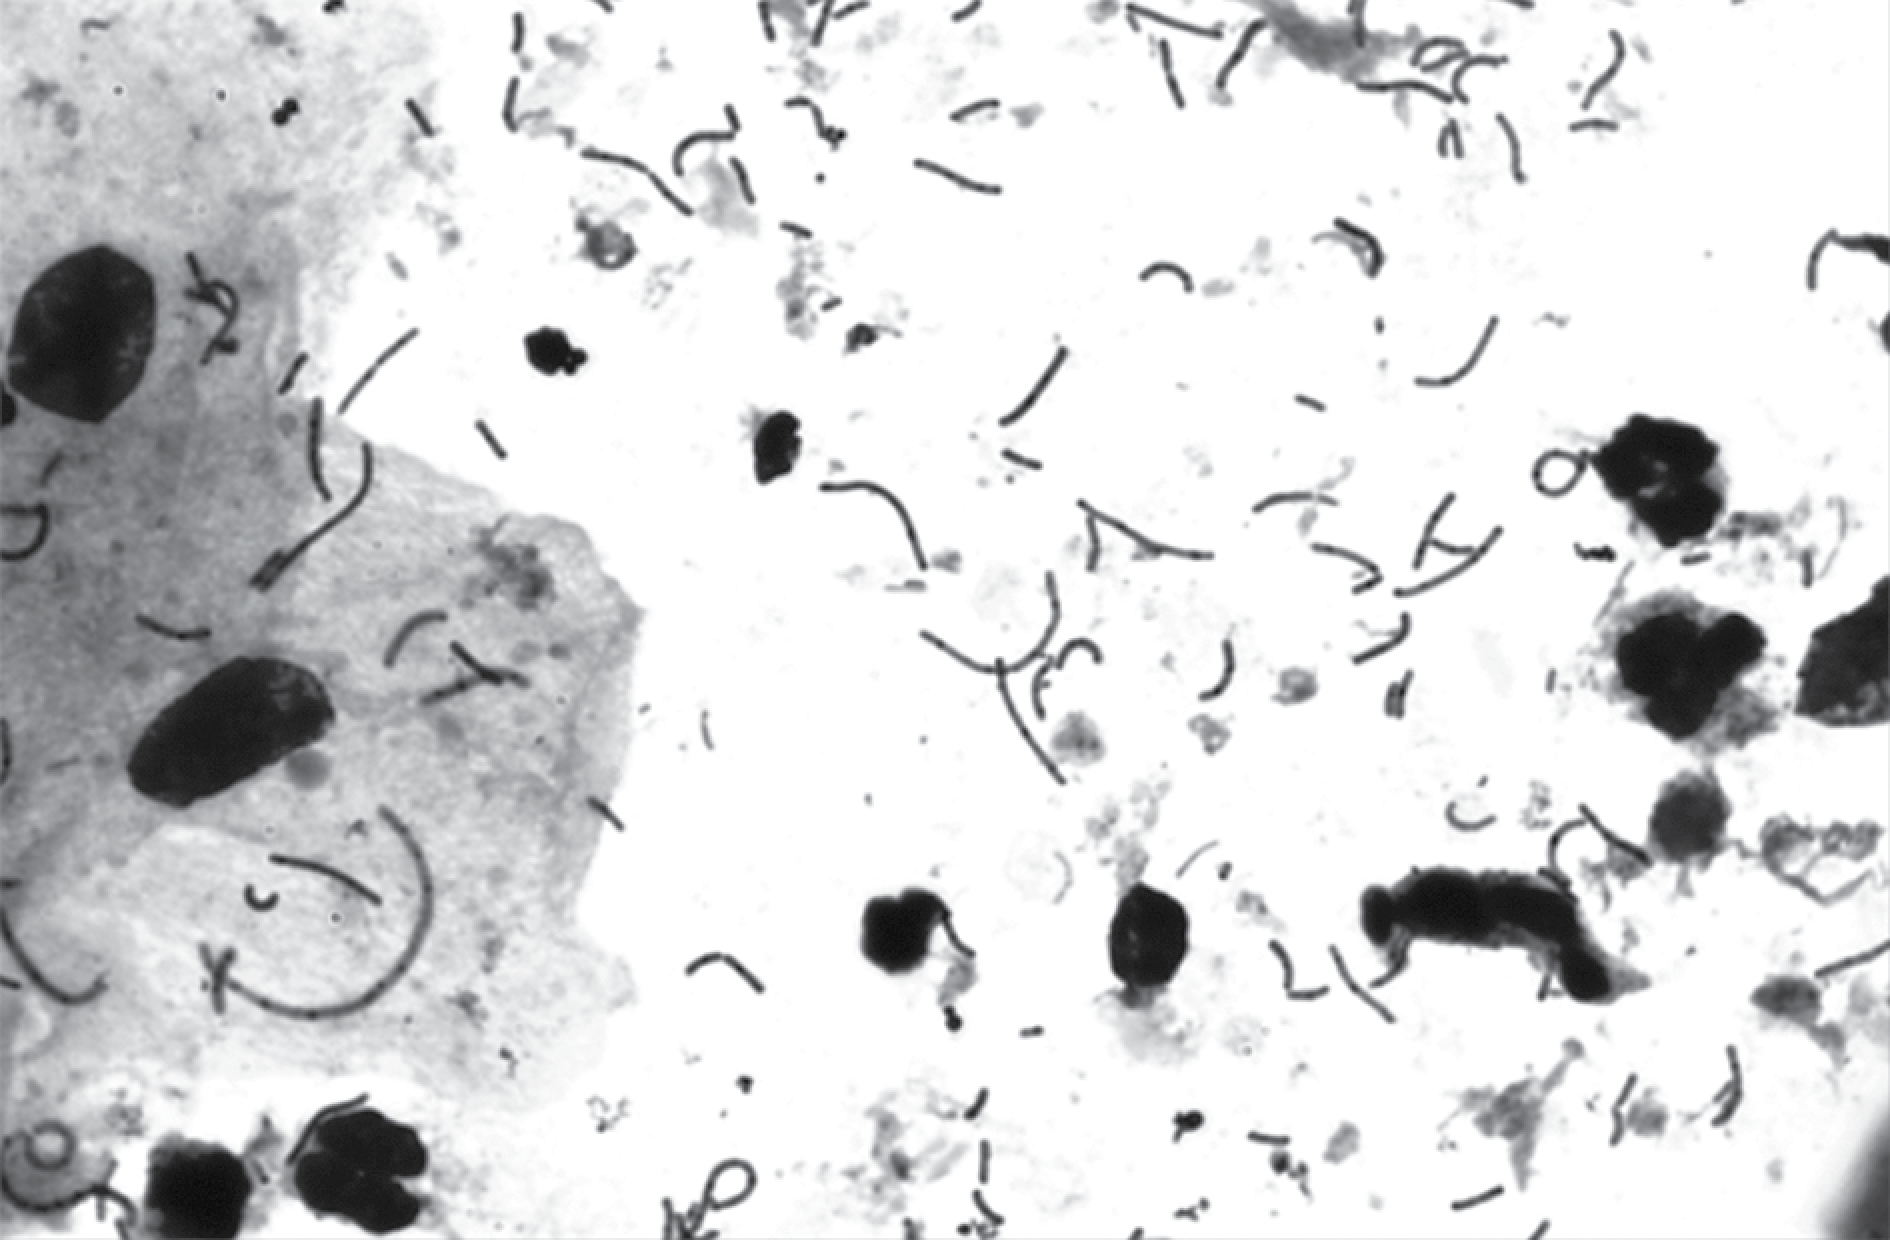

Для подтверждения установленных связей был проведен корреляционный анализ Спирмена, который показал следующие результаты: была обнаружена положительная корреляция между L. crispatus и толщиной палочек, тенденция к отрицательной корреляции между L. jensenii и толщиной палочек, тенденция к отрицательной корреляции между L. iners и толщина палочек, тенденция к отрицательной корреляции между L. jensenii и формой палочек, тенденция к отрицательной корреляции между L. vaginalis и формой палочек. Иными словами, вероятно, толстые палочки, обнаруживаемые в обзорных гинекологических мазках, относятся к виду L. crispatus (рис. 4), а тонкие — к видам L. iners и L. jensenii (рис. 5). При обнаружении в мазке прямых палочек, предположительно, мы имеем дело с L. jensenii и L. vaginalis.

Рисунок 5. Фотография обзорного гинекологического мазка, окраска метиленовым синим, увеличение ×100

Figure 5. Photograph of an overview gynecologic smear, stained with methylene blue, magnification ×100

Примечание. Тонкие палочки, которые при типировании были идентифицированы как L. iners.

Note. Thin bacilli that were identified as L. iners during typing.